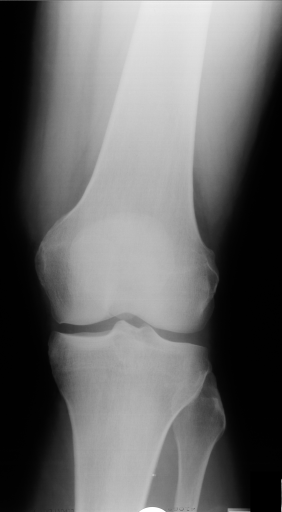

Figure 3 shows some samples images from IRMA dates along with their corresponding IRMA codes.